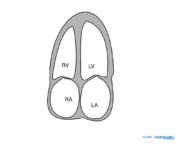

| 12:50, 26 April 2009 | AP4CH.svg (file) |  |

38 KB | April | 1 | |